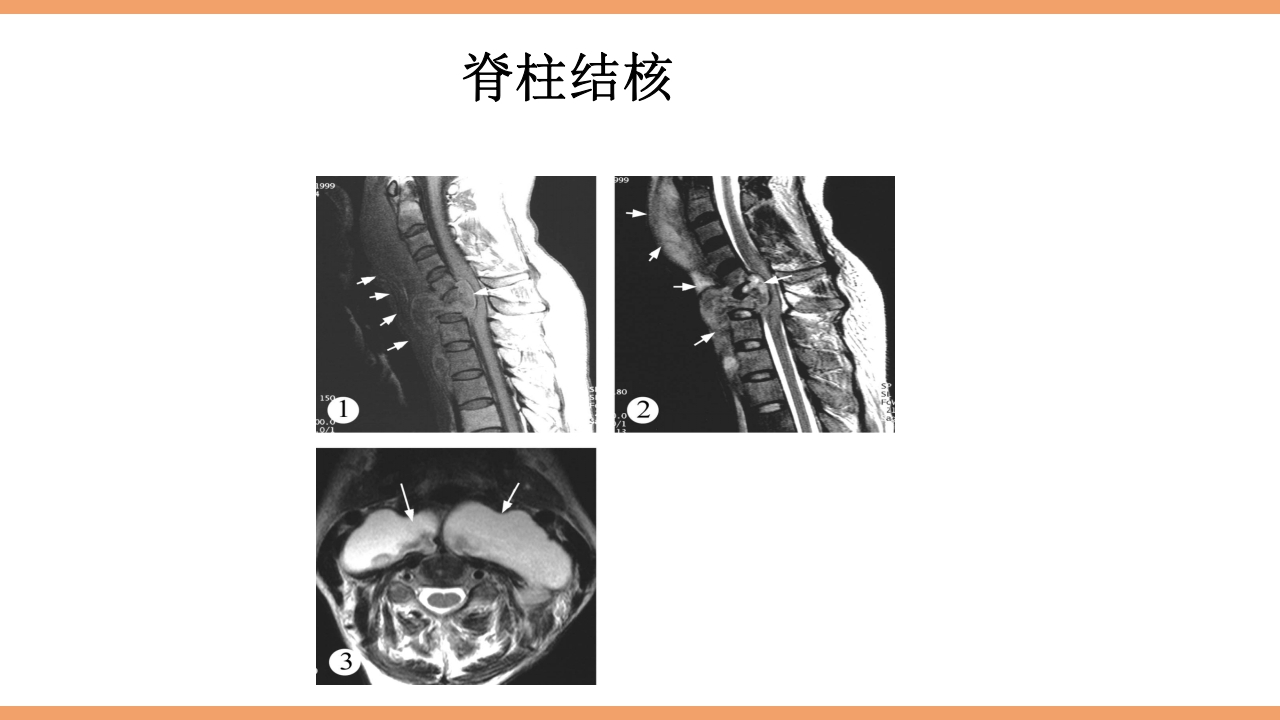

CONTENTS 目 录 1 结核简介 2 脊柱结核概论 3 病灶形成和发展 4 解剖位置 5 病理病因 6 分型 7 临床表现及症状体征 8 影像学及实验室检查 9 治疗 10 护理 11 治愈标准 12 出院指导 西医谓之为: 骨、关节结核:结核病菌侵入骨或关节内并在其中繁殖,出现 一系列的病理改变。 中医谓之为: 骨痨:由于结核杆菌侵入骨或关节而引起的化脓性病变,其病 发于骨,消耗气血津液,导致形体虚赢,缠绵难愈故其名为骨痨。 成脓破溃后,脓液中伴败絮状痰样物,可流窜他处形成寒性脓肿, 又名流痰。骨痨发于脊柱称之为脊柱痨、龟背痰。 胸椎结核为龟背痰,腰椎结核为肾俞虚 痰,骶尾椎结核为尾闾发。 1.脊柱结核是一种继发性病 变,约90%继发于肺结核.少 数继发于消化道结核、胸膜 结核或...